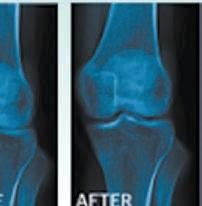

Dr. Angelina Alejandro, NMD (Naturopathic Physician)

Join us for a FREE GOURMET DINNER Seminar with leading Natural Medicine and Wellness Expert, Dr. Angelina Alejandro, NMD (Naturopathic Physician)

Dr. Alejandro will tell you about the latest methods, breakthroughs and time-tested strategies that will help you permanently and safely remove unwanted weight while quickly reclaiming your health, your youth and your life!

✔ Learn how Hormone Imbalances - man or woman - can distort your midsection into a large belly and prevent weight loss, even with dieting and exercise.

✔ Understand why “Counting Calories” doesn’t work, and the biggest mistakes people make with exercise that prevents weight loss.

✔ Clear approaches that inspire, are compatible with full lifestyles, and which show quick results with long-term success.

✔ Discover what really works for permanent loss of bulges and belly fat, safely and healthfully!

SEMINAR DATE: THURSDAY, MARCH 2ND 2017

418-2653 CANTINA LAREDO 7361 E. Frank Lloyd Wright Blvd. Scottsdale, AZ 85260

✔ Understand why prevention is key, what is necessary for “ageless” living well into our “senior” years. (NOW is the time!) Call

“I began my program with a goal of losing 45 pounds. I’ve not been hungry between meals (fortunately!) and I DO feel terrific! To date I’ve lost 27 pounds and 3 dress sizes. I started at a size 16 and am now a size 10 with some as small as size 8 and I’m not done. If you’ve not had success previously, Dr. Cole might be your answer! Don’t you owe it to yourself to sleep well, feel good and be healthy?”

-Linda Bacon